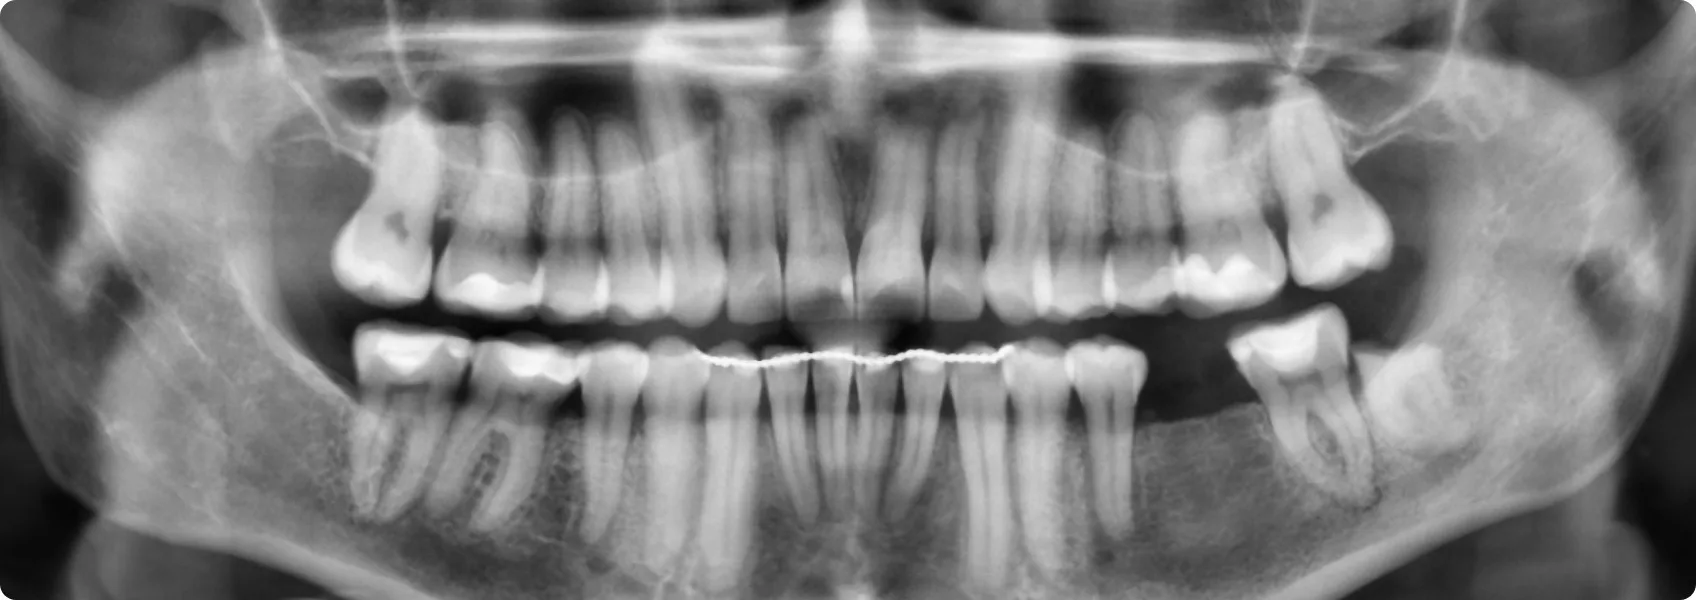

U Pacjentki fluoroza wystąpiła w obrębie zębów górnych oraz dolnych. Do NDC zgłosiła się po zakończonym leczeniu ortodontycznym w innej klinice.

Dr n. med. Ewa Chomik zaproponowała pełną rekonstrukcję funkcjonalno-estetyczną obu łuków za pomocą licówek.

Licówki to cienkie płatki porcelany, które przykleja się do przedniej strony oszlifowanego zęba. Zęby Pacjentki trzeba było jednak wybielić aż o 5 odcieni. Do tego wadliwa budowa szkliwa z fluorozą nie pozwalała na przyklejenie klasycznych licówek (adhezyjnych).

Wax-up ląduje w artykulatorze. Trzeba sprawdzić funkcję!

Artykulator to mechaniczne urządzenie, które pozwala technikowi symulować ruchy żuchwy Pacjenta, jakby model zębów gryzł i poruszał się tak samo jak w prawdziwych ustach. Artykulator musi być wyjątkowo precyzyjny. Urządzenie przenosi dokładne ustawienia i miary pobrane z twarzy Pacjenta.

Jeśli wax-up nie uwzględnia funkcji, może się okazać, że Pacjent zetrze nowe licówki, ceramika pęknie lub pojawi się ból w stawie skroniowo-żuchwowym.